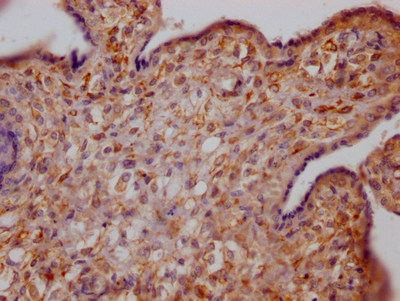

IHC image of CSB-RA978909A0HU diluted at 1:100 and staining in paraffin-embedded human placenta tissue performed on a Leica BondTM system. After dewaxing and hydration, antigen retrieval was mediated by high pressure in a citrate buffer (pH 6.0). Section was blocked with 10% normal goat serum 30min at RT. Then primary antibody (1% BSA) was incubated at 4℃ overnight. The primary is detected by a Goat anti-rabbit IgG polymer labeled by HRP and visualized using 0.05% DAB.